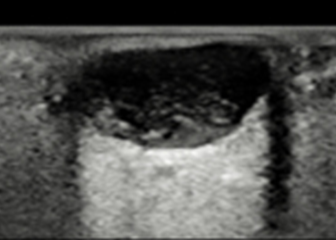

초음파 영상촬영을 통해 주위 조직과의 관계, 크기, 모양 등을 면밀하게 파악합니다.